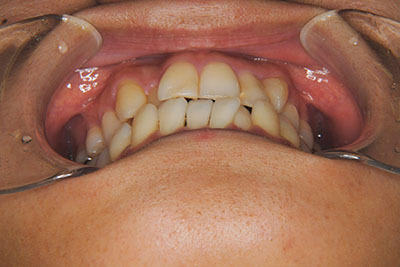

おとなの方でも矯正治療をあきらめないでください!

矯正歯科治療は子供の頃だけしかできない……

子供の頃に比べ大人になったら治療期間がすごく長い……

というようなイメージをお持ちではありませんか?

子供の頃に矯正治療を行う方が治療期間が短く済むというのは、確かですが、矯正治療は患者様の意識も重要です。

いくら歯が動き易くとも、本人がやる気でなければ効果は出ませんし、むし歯発生のリスクも高まります。おとなの方は顎の成長が終わっているため、治療の計画が立てやすいとも言えます。「もう大人だから…」とあきらめず、一度ご相談ください。